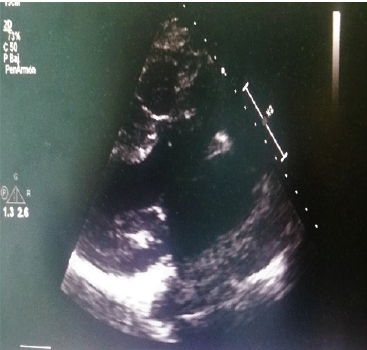

31-year-old man history of stroke in childhood. He starts with progressive dyspnea functional class II 6 months ago. Physical examination shows a meso systolic aortic murmur II / IV of ejection intensity without irradiation, and symmetrical radial pulses. TEE (transesophageal echocardiogram) (Figure 1) Diastolic diameter LV (left ventricle) 47 mm, DSVI (systolic diameter of the left ventricle) 30, VTD (tele diastolic volume) 170, LVEF (left ventricular ejection fraction) 53%, without segmental mobility alterations. Trivalve aortic valve with subaortic impeller of 5 mm to 2 mm of the ring, maximum speed 2.6 m/s, maximum gradient of 27, average gradient of 14 mm.